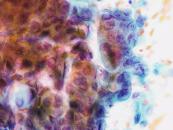

第35回日本臨床細胞学会九州連合会学会(宮崎)スライドカンファレンス症例4

種別:婦人科

出題:熊本大学病院 病理診断科・病理部 佐野直樹 先生

| 年齢 | 60歳代 | 性別 | 女性 |

|---|---|---|---|

| 採取部位 | 子宮頸部 | 採取方法 | 擦過 |

| 検体処理法 | 従来法 |

臨床所見

既 往 歴:糖尿病、脂質異常症

現 病 歴:4年前に帯下の増加を自覚し受診し、子宮頸部細胞診でNILMの判定。今回、下腹部痛を主訴に受診し、腟鏡診では病変は不明瞭だったが、双合診で子宮頸部全体に硬結あり。

| 正解 | 5.胃型粘液性癌 |

▼選択肢及び投票結果

| 1.化生細胞および修復細胞 | 3件 | (3.1%) | |

| 2.重層性粘液産生上皮内病変(SMILE) | 38件 | (39.2%) | |

| 3.通常型腺癌 | 10件 | (10.3%) | |

| 4.明細胞癌 | 26件 | (26.8%) | |

| 5.胃型粘液性癌 | 20件 | (20.6%) | |

| 投票総数 | 97件 | (100%) |